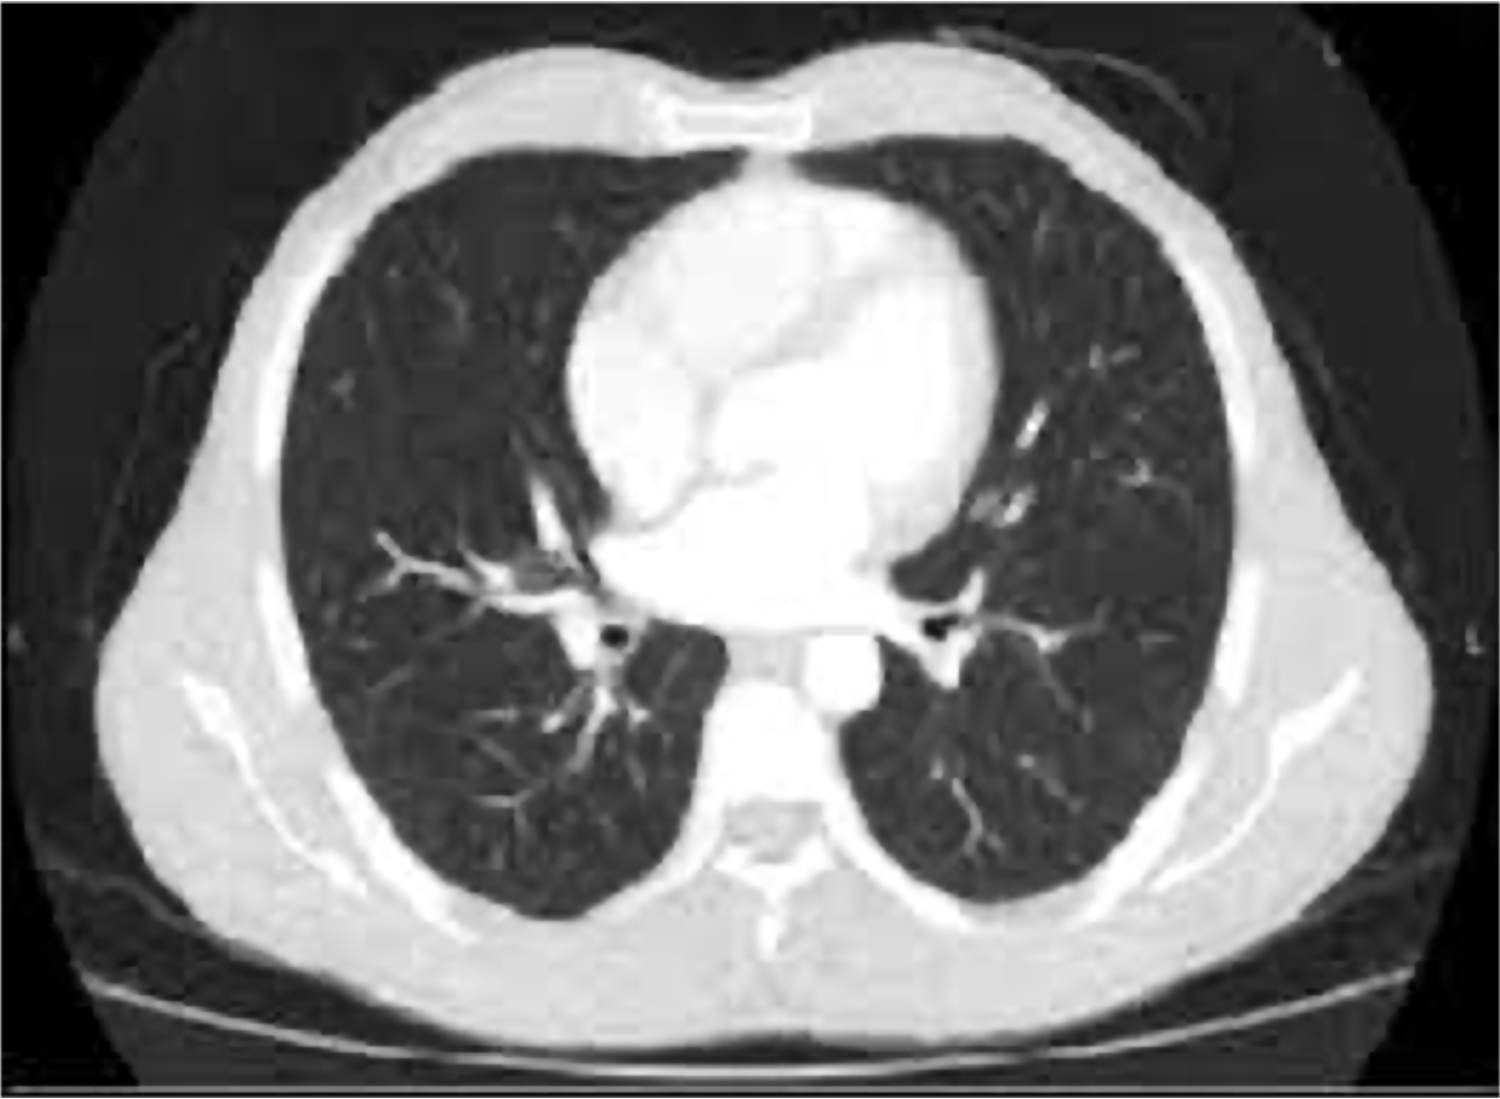

TACR

Exploraciones complementarias

Solicitamos nueva evaluación del paciente, realizando varias exploraciones complementarias.

TCAR frontal

TCAR desde arriba